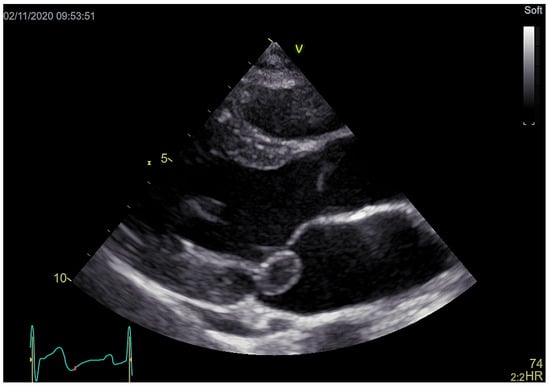

Echocardiography revealed an 11 × 17 mm large pedunculated mass attached to the posterior leaflet of mitral valve (Figure 2, video 1: https://vimeo.com/548176262 and video 2: https://vimeo.com/548178575) with minimal insufficiency.

Figure 2. 11 × 17 mm large pedunculated mass attached to the posterior leaflet of mitral valve.